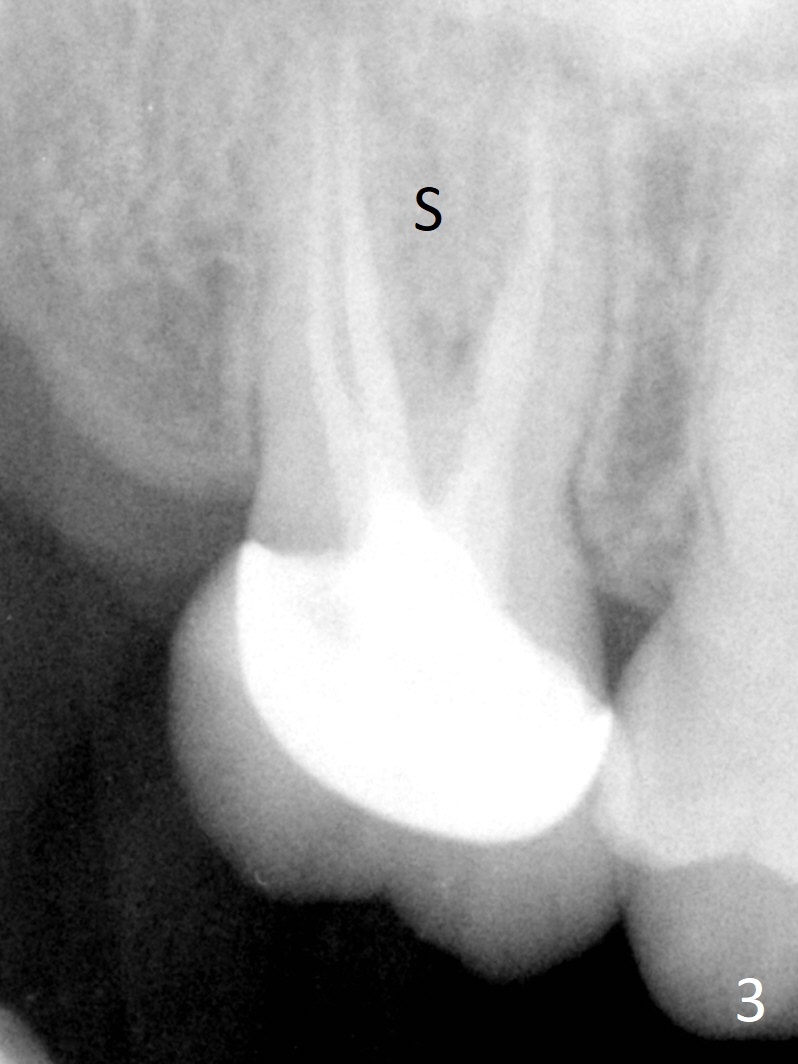

A 58-year-old woman has had RCT done at #2 for several years. The roots are trifurcated with sufficient bone height (Fig.1-3). Recently the tooth becomes symptomatic with formation of a distal fistula (Fig.4). After extraction, the septum (Fig.5 S) may be wide enough for initial drill (Fig.6). If not, resection the thin part of the septum (Fig.7 red line, with small or medium Rongeur) and use the initial drill (Fig.8). Anyway, take PA immediately to avoid sinus membrane perforation. If possible, adopt single drill technique.